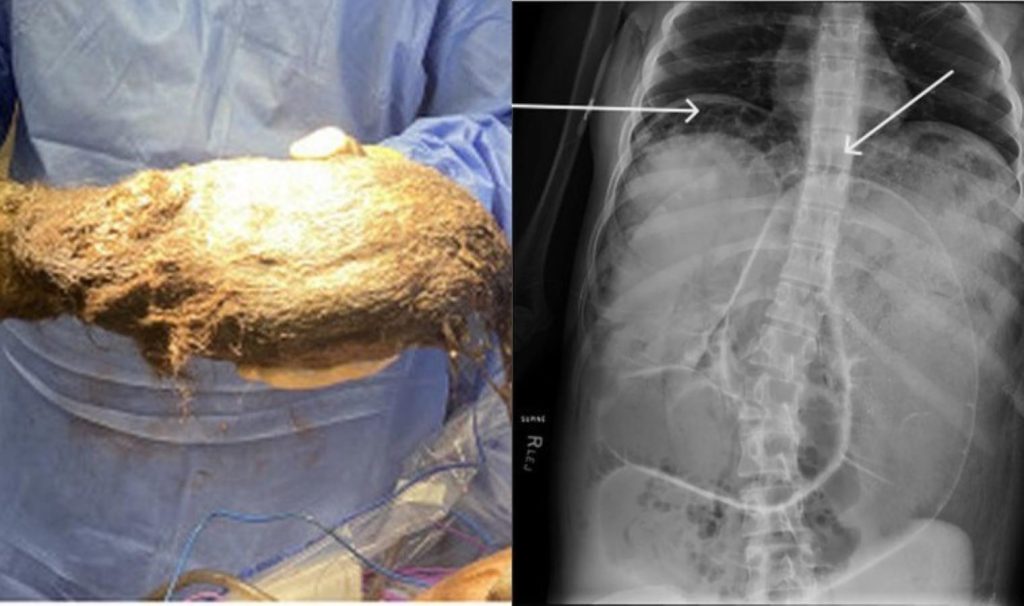

Karmaşik bir orörün akabinde hekimler, Kuzin Midesinden 2.468 gram yukünde bir Kil Yumağ.

Gerçekişşöten Operason Sonrasonda Kil Yumalil Aindi, Kizin Durumunun Uygun Ondusununutili.

Rapunzel Sendromu, Insanlarda Saç Yeme Hastali (Trikofaji) Nedeniyle Görülen Birp Birp Birp Denizkak Rahatizkez. Hastalet, Grimm Kardeşlerin Masalezizdaki Uzun Saçli Karakter Rapunzel’den Esinlenerek Isimlendirilmiş. Trikofaji, Kimi Durumlarda, Tekrarli Saç Yolma Davranşyeyla Kendini Gösteren Trikotilomani Ile ilişkilendirilir.